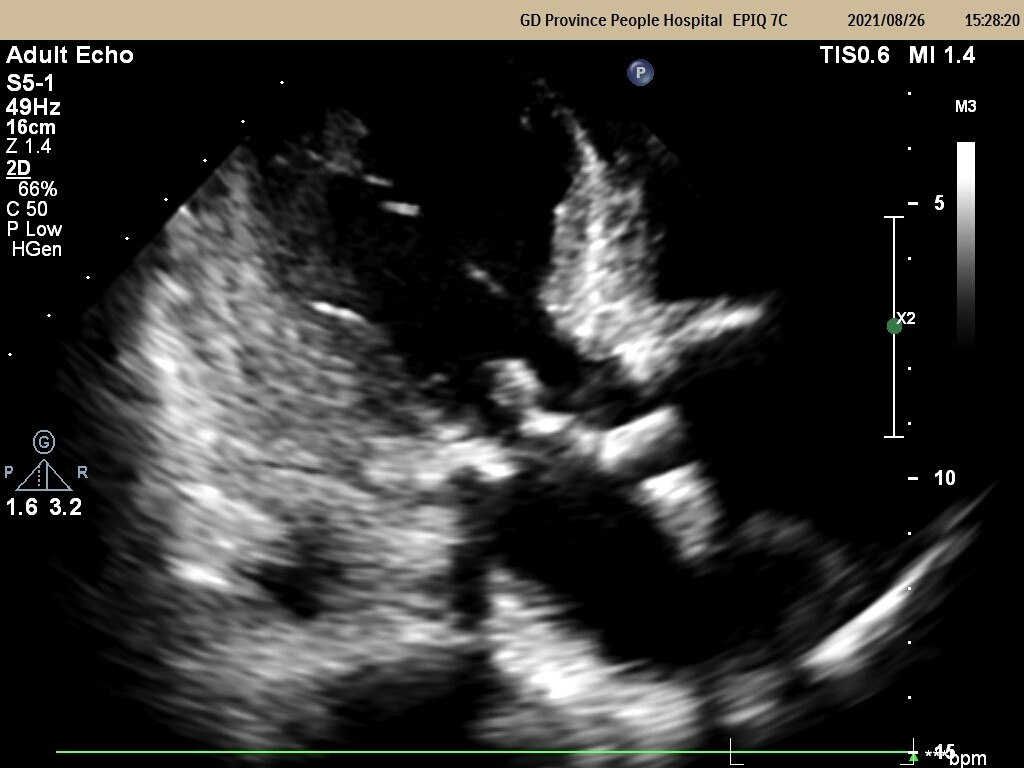

重主动脉瓣口流速 4.9m/s;峰压差 98mmHg;平均压差57mmHg;LVEF 55%

重度主动脉瓣狭窄并中度反流 轻度二尖瓣反流 轻度三尖瓣反流

少量心包积液

升主动脉明显扩张

主动脉瓣及二尖瓣毛糙(赘生物不明显),建议必要时行经食道三维超声进一步评估瓣膜情况